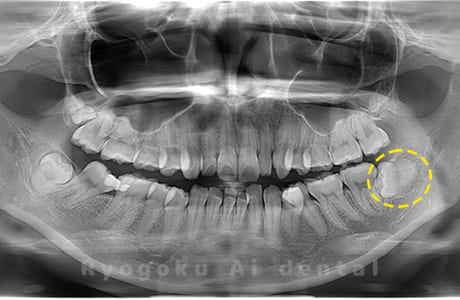

Case09

-

- 原因

- 下顎左の水平埋伏智歯

- 治療内容

- 下顎左の水平埋伏智歯を抜歯したケースです。

<リスク・副作用>

手術後は痛み、腫れ、痺れなどの副作用が生じる場合があります。